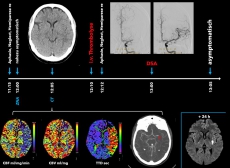

Patienten und Patientinnen mit einem akuten Schlaganfall werden durch das Team der Zentralen Notaufnahme diagnostiziert und den Akuttherapien zugeführt – der intravenösen Thrombolyse und, bei großen Gefäßverschlüssen, der endovaskulären Thrombektomie durch die Neuroradiologie (Abbildung 2). Anschließend übernimmt ein spezialisiertes Team aus vaskulären Neurologen und Neurologinnen, Pflegepersonal sowie Therapeuten und Therapeutinnen (Ergotherapie, Logopädie, Physiotherapie) die Behandlung auf der Stroke Unit. Aufgabe der Stroke Unit ist es, zum einen optimale sekundärpräventive Maßnahmen zu ergreifen um ein Rezidiv zu verhindern, zum anderen neurologische Defizite frühestmöglich umfassend zu behandeln und, wenn notwendig, anschließende Rehabilitationsmaßnahmen vorzubereiten.